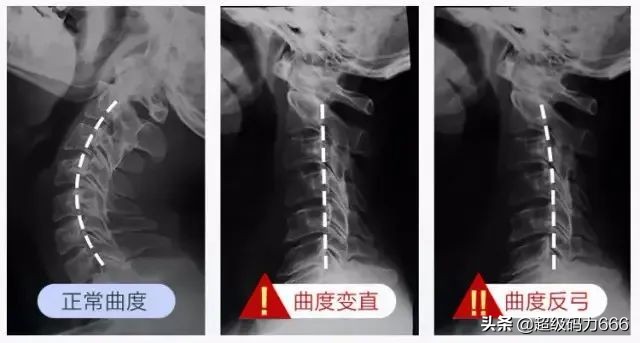

错误的坐姿和不健康的习惯,颈椎就会变直,甚至会出现反弓,直接压迫颈部。

颈椎病、疲劳头痛、肩颈、腰椎等疾病说来就来。

其实,很多人都知道颈椎牵引是目前放松颈椎较好的方式之一。

长期使用,我们就能缓解肩颈疼痛,颈椎恢复正常的生理曲线。